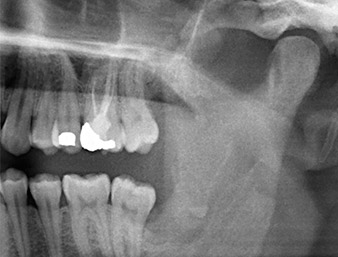

Ya en la ortopantomografía, se constató que había un resto radicular de la región 38 muy cerca del nervio alveolar inferior (figura 1). La raíz se había fracturado durante la osteotomía, pero el primer odontólogo que había tratado al paciente no había extraído esta debido a la presencia de dolor durante la operación.

En la imagen en 3D (tomografía volumétrica digital) se constató que el resto radicular se encontraba muy desplazado en sentido distocaudal en la transición situada entre la porción horizontal y la ascendente del maxilar inferior (figura 2).

La anamnesis del paciente era favorable (no fumador, 26 años) para garantizar el éxito de la aplicación. Como la ortopantomografía mostró que el resto radicular se encontraba muy cerca del nervio alveolar inferior, se realizó también una tomografía volumétrica digital (6).